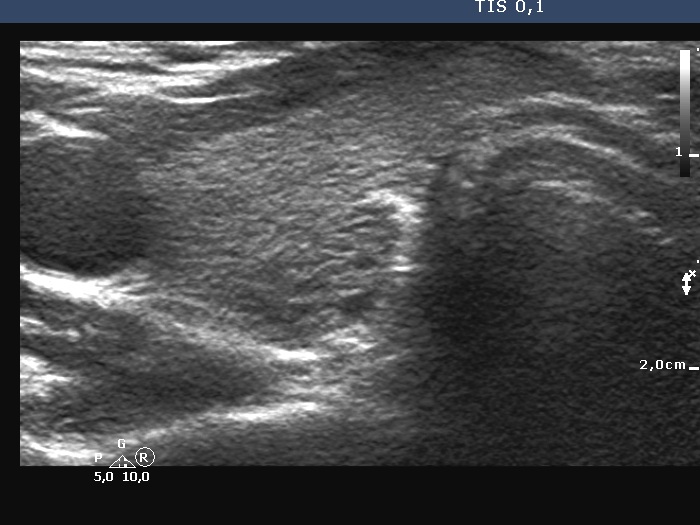

Introduction - case 816 (ultrasonographic picture 3)

Right lobe, another transverse scan - enlarged view. In this section the dorsal part of the lobe does not seem to be nodular. Note that just dorsal to the hyperechoic connective tissue, the thyroid is hypoechoic.